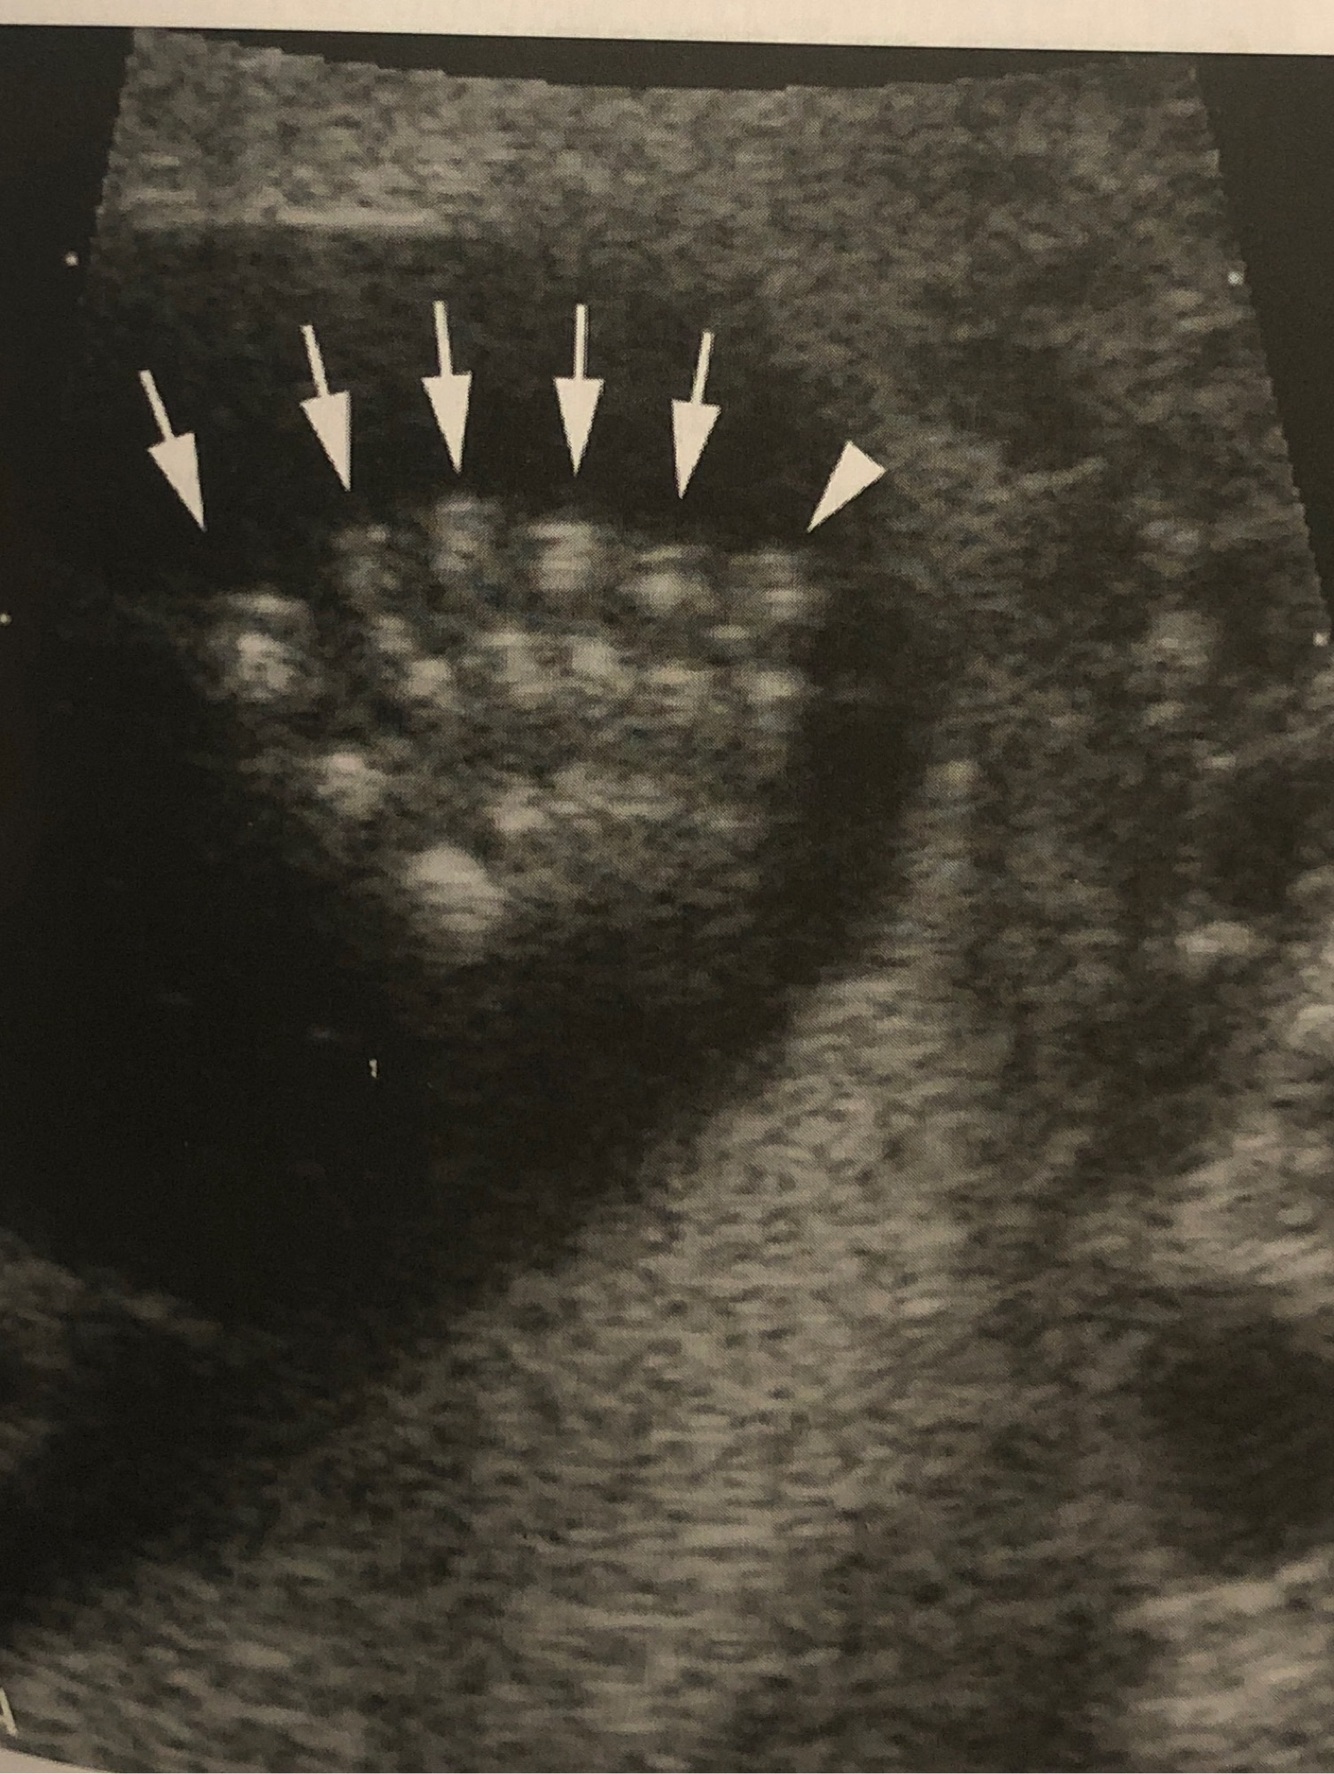

Q

What abnormality is this? What is it associated with?

A

Polydactyly. Trisomy 13/Patau